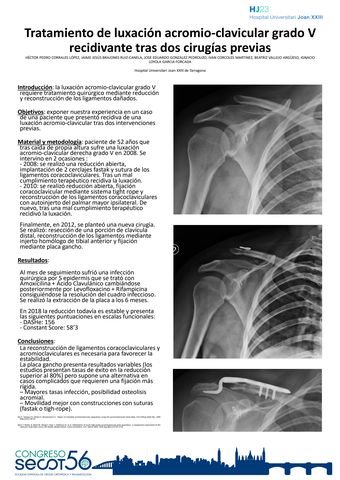

Tratamiento de luxación acromio-clavicular grado V recidivante tras dos cirugías previas

Título: Tratamiento de luxación acromio-clavicular grado V recidivante tras dos cirugías previas

Autores:

HÉCTOR PEDRO CORRALES LÓPEZ, JAIME JESÚS BRAJONES RUIZ-CANELA, JOSE EDUARDO GONZALEZ PEDROUZO, IVAN CORCOLES MARTINEZ, BEATRIZ VALLEJO ARGÜESO, IGNACIO LOYOLA GARCIA FORCADA